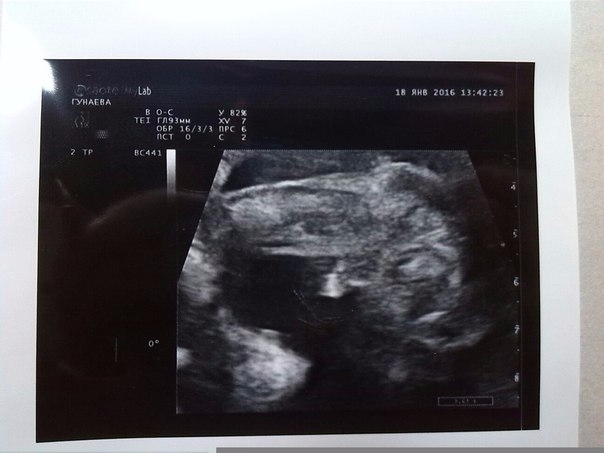

Ааааа ,день Х настал ! У Нас родится СЫН!!! Первые фотографии нашего сыночка !

ААаааа я наконец то дождалась это дняя !!! Смотрели нашу кроху .Мне ничего не показали ,это меня конечно разочаровало ,но папа что то увидел !!))) Главное что все хорошо ! Немного с запозданием первый скрининг у меня ,Я та точно знала день зачатия 16- сентября (11 нед и 5 дней ) Срок 13 и 5 ,молодец доктор с точностью до дня все правильно сказал ! Результат крови узнаю через неделю !